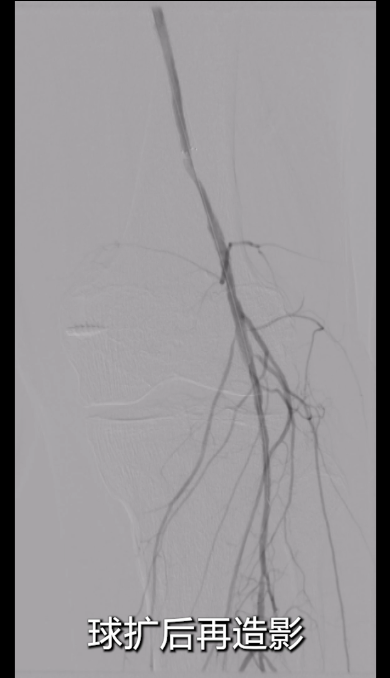

吸栓后即时手推造影:可见支架内形成基本流入道及流出道,血流初步恢复。

即时造影:支架贴壁良好,病变段完全覆盖,膝下腓动脉及胫后动脉显影明显改善,胫后动脉血流可至足趾;